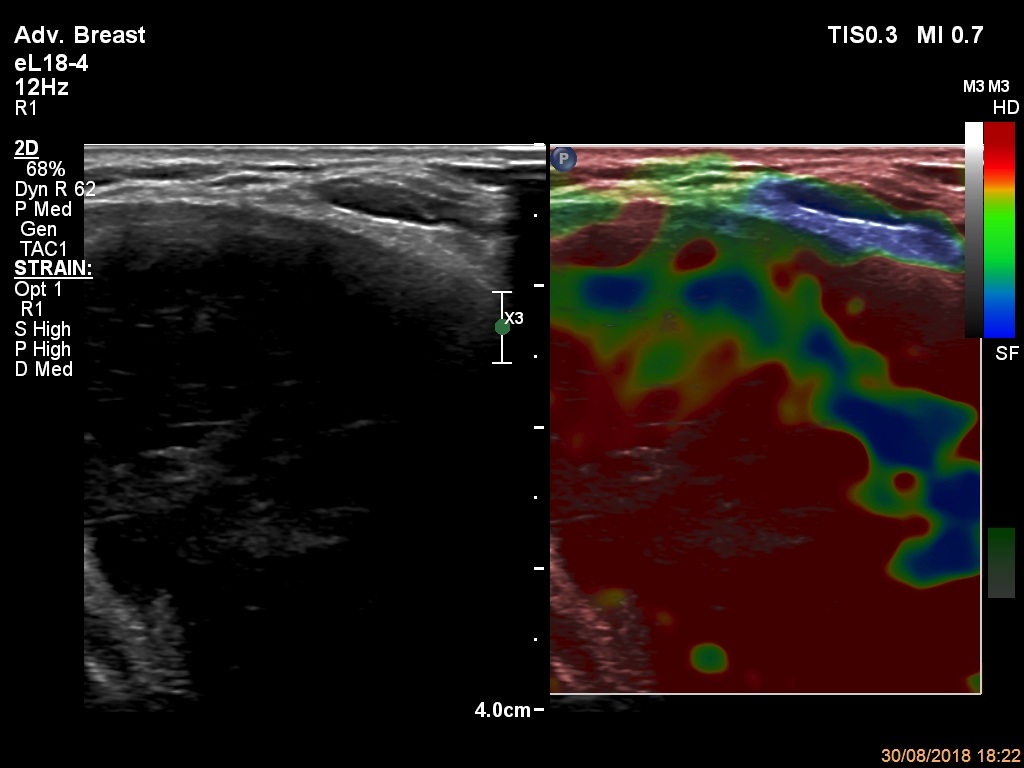

Thyroid cancers - case 1676 (ultrasonographic picture 10)

Left lobe, longitudinal scan, elastography. The lesion is very hard.